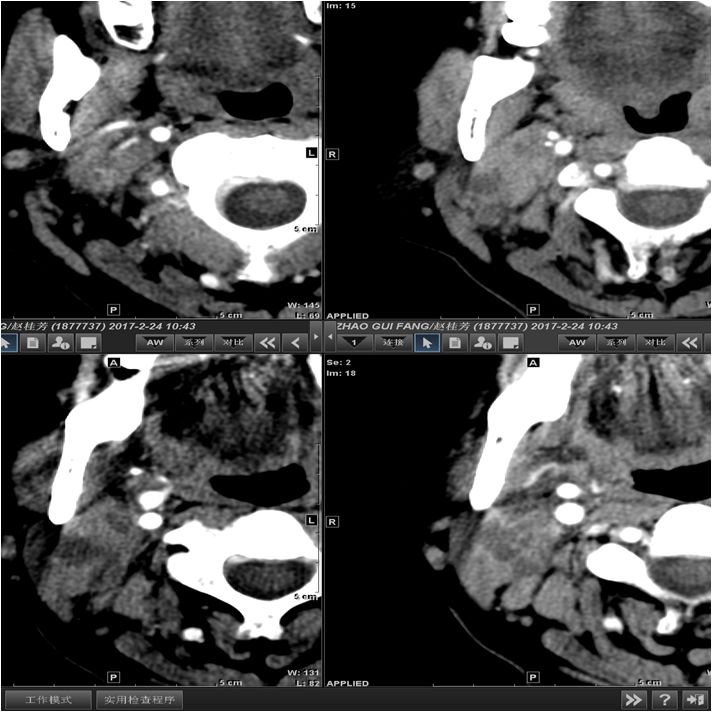

15 多间隙受累

(1)左下后牙疼痛11天余,颈部肿胀10天。

(2)右侧颌面部弥漫性肿胀1月余。